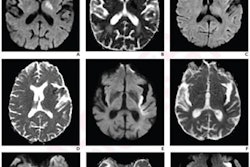

A team led by senior author Dr. Johanna Fifi assessed results from 226 stroke patients who underwent endovascular thrombectomy between January 2017 and February 2020. Of these, 106 were treated by the mobile interventional stroke team (MIST), and 120 were treated at the hospital. The group compared 90-day functional outcomes between the two patient groups, tracking results by treatment within six hours of stroke onset and six hours after.